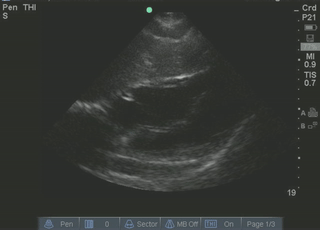

Normal subxiphoid (subcostal) view

| current | 12:44, 18 July 2016 | 320 × 230 (33 KB) | Neil.m.young (talk | contribs) | Normal subxiphoid (subcostal) view |